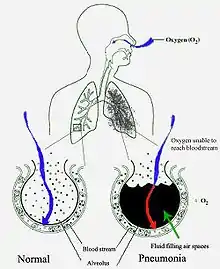

Lungebetændelse eller pneumoni er en betændelsestilstand i lungerne. Den påvirker især de mikroskopiske luftsække, der hedder alveoler.[1][2] Sygdommen skyldes som regel en infektion med virus eller bakterier og mindre hyppigt andre mikroorganismer, visse lægemidler og andre lidelser såsom autoimmune sygdomme.[1][3]

Lungebetændelse starter typisk som en infektion af de øvre luftveje, som så flytter sig ned i de nedre luftveje.[31]

Bakterielt

De fleste bakterier når lungerne/svælget ved indånding af små mængder organismer fra hals eller næse.[11] Halvdelen af alle normaltfungerende mennesker indånder små mængder væske/stof til lungerne, når de sover.[18] Der findes altid bakterier i halsen, men mulige smittebærere er der kun på bestemte tider og under bestemte forhold.[18] Et fåtal af disse bakterier, såsom Mycobacterium tuberculosis og Legionella pneumophila når lungerne via kontaminerede, luftbårne dråber.[11] Bakterier kan også spredes med blodet.[12] Når først bakterierne er i lungerne, kan de invadere mellemrummene mellem celler og mellem alveoler, hvor makrofagerne and neutrofile (defensive hvide blodlegemer) prøver at gøre bakterierne inaktive.[33] Neutrofilerne udskiller også cytokiner, som aktiverer immunforsvaret.[34] Dette giver feber, kulderystelser og træthed, som er så velkendt ved bakteriel lungebetændelse.[34] Neutrofiler, bakterier og væske fra de omgivende blodbaner fylder alveolerne, hvilket kan ses på røntgenbilleder af thorax (brystkassen).[35]

Respirations- og kredsløbsinsufficiens

Lungebetændelse kan medføre respirationsinsufficiens (lungesvigt) ved at udløse akut respiratorisk distress-syndrom (ARDS), som skyldes en kombination af infektion og inflammatorisk respons. Lungerne fyldes hurtigt med væske og bliver stive. Denne stivhed kombineret med svært nedsat iltoptagelse som følge af væsken i alveolerne kan kræve lange perioder med mekanisk respiration, for at patienten kan overleve.[22]